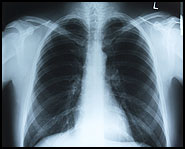

What is asthma?